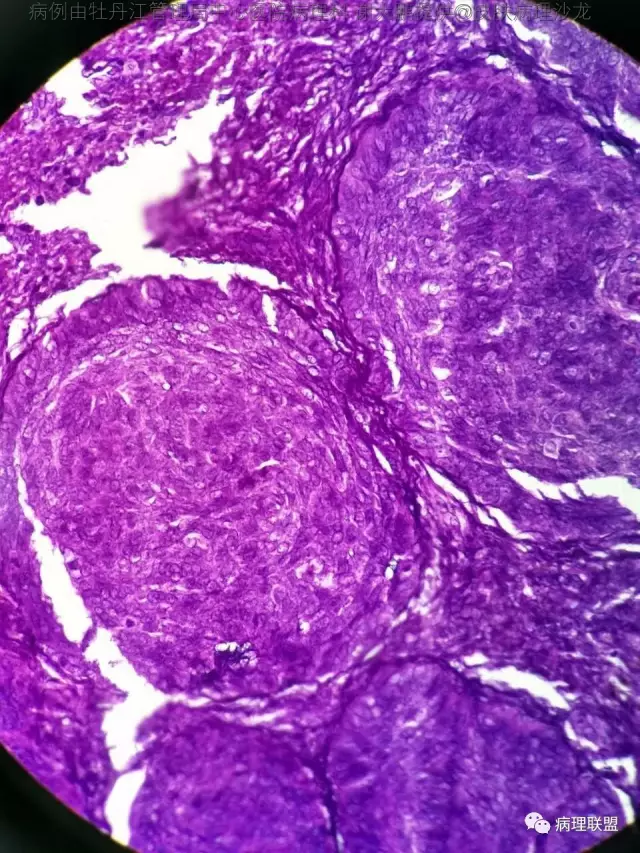

69岁,鼻翼肿物2年,1.5厘米大小,麻烦老师们帮忙看看,谢谢(病例由牡丹江管理局中心医院病理科 谢大鹏提供,致谢!)